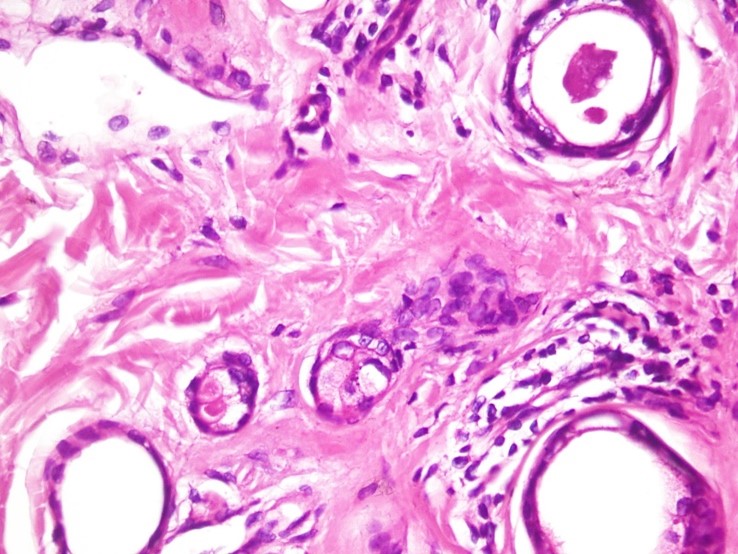

Differential diagnosis that was considered for this case were acne vulgaris, sebaceous hyperplasia, milia, lichen planus, xanthelasma and urticaria pigmentosa. A punch biopsy was obtained from one of the trunk lesions and histology findings showed no significant changes in the epidermis, however it showed some ducts and small cysts and strands of epithelial cells lined by flat or cuboidal cells and filled with homogenous material in the dermis. These findings were compatible with eccrine tumor in the dermis which was consistent with syringoma (Figure 2). So according to the clinical and laboratory findings, the patient was diagnosed with generalized eruptive syringoma.

Figure 2: Biopsy specimen from a trunk lesion. some ducts and small cysts and strands of epithelial cells lined by flat or cuboidal cells and filled with homogenous material in the dermis. (Original magnifications ×10).